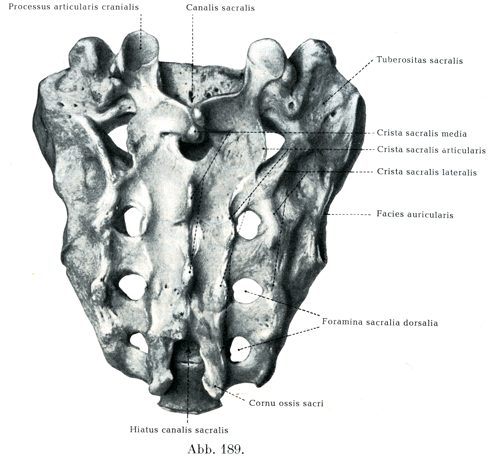

背方の凸出した面すなわち後面Facies dorsalisは,よく発達した例では正中線上に中仙骨稜Crista sacralis mediaという隆起があって,そこに4つのかなり強大な突起が出ている.この突起がつまり仙椎の棘突起の端なのである.それほどはっきりしたものでないが,その左右に1列ずつ縦に並ぶ凹凸は,関節仙骨稜Crista sacralis articularisとよばれ,各側の関節突起が癒合した部分に当る.一番上の関節突起すなわち上関節突起Processus articularis cranialisは自由端をなしていて,第5腰椎の下関節突起を外側から抱きこんでいる.また一番下の退化的な関節突起は各側で角のように下方へ伸びているので,仙骨角Cornu ossis sacriという名がついている.両仙骨角と,最下またはその1つ上の棘突起との間に,門のような形の仙骨管裂孔Hiatus canalis sacralisが開いて,脊柱管の仙骨部すなわち仙骨管Canalis sacralisに通じている.関節仙骨稜の外側には各側に4つの後仙骨孔Foramina sacralia dorsaliaがみられる.

[図189]仙骨(男性)の後面(4/5)